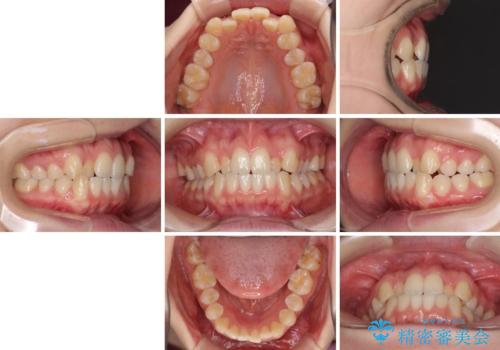

前歯のクロスバイトをインビザライン矯正で改善

- 前歯のデコボコと上下のクロスバイトを気にして来院された患者様です。

インビザラインを用い、IPR(歯と歯の間を削る)と歯列全体を拡大させることで、歯並びを整えていくこととしました。

上の前歯が下の前歯を乗り越える際、奥歯がほとんど咬めない時期があり、乗り越えた後も、インビザライン特有の奥歯の咬みにくさが続きました。

咬み合わせ改善のために治療期間を要しましたが、最終的に奥歯はしっかりと咬めるようになりました。